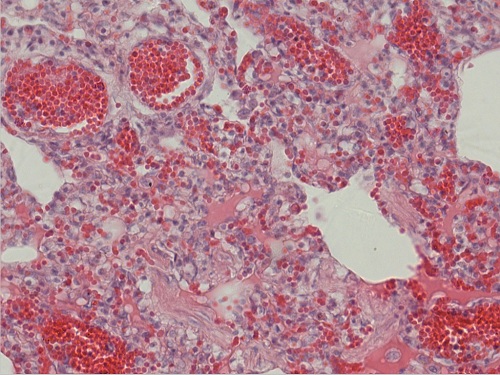

肺充血(有出血)10X40